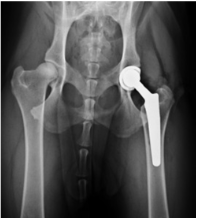

What is occuring here?